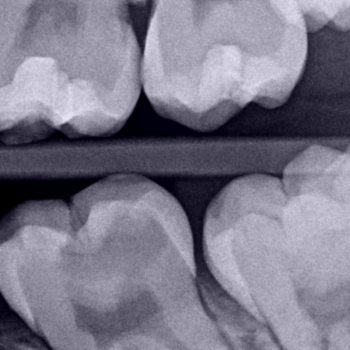

The patient attended reported short-term pain in tooth no. 19 (Fig. 1). Through radiography, a clinical assessment, and an analysis of the patient’s clinical history, an extensive carious lesion was diagnosed (Fig. 2) as the cause of the pain, due to a process of reversible pulpitis.

Fig. 2. Bite radiograph shows evidence of a carious lesion of tooth 19. Undermineralized tissue is found close to the mesial pulp horn.